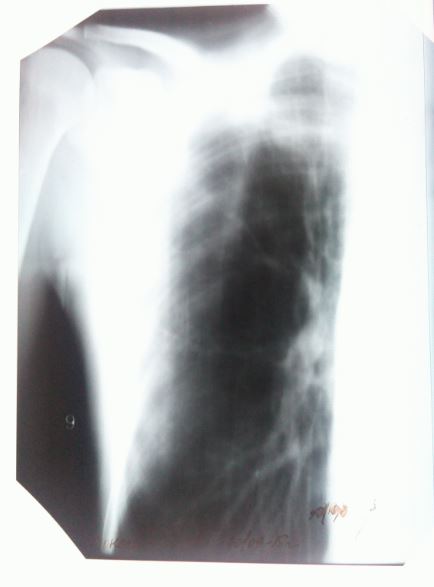

Здравствуйте,еще раз. Как сказала врач, в направлении там где написано " диагноз " - это то что показывают снимки.

Как еще врач говорит. По анализам все хорошо , по диаскинтест - отрицательно. Видимых симптомов нет , при осмотре-прослушивании тоже все хорошо. Как тогда может быть такой диагноз? Нет ни температуры.ни отдышки,ни головной боли,вес не теряла,не худела резко,в семье ни у кого такого не было.на учете не состояла. просто как так может быть что по снимкам развие " болезни " есть , а по анализам и тесту нет ?

Здравствуйте. Да, действительно случаи бывают разные. Тем и коварен уберкулез, что распознать его удается не всегда, и симптомов явным может не быть, и анализы могут не показывать всей картины. Но диагноз врач выставил на законных основаниях - изменения в легких типичны для туберкулеза. Консультируйтесь в областном центре, можно также сделать КТ (компьютерную томографию), ведь этот метод более точен, чем рентген.